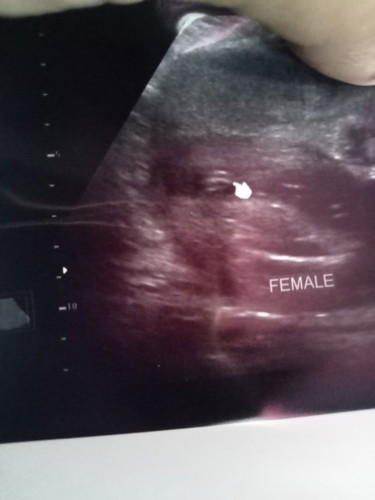

อัลตร้าซาวด์เพศ

ตั้งความหวังไว้มากว่าคนที่2จะเป็นลูกสาว ถามหมอ3ครั้งดู3ครั้งก็บอกว่าเป็นกลีบได้ลูกสาวแม่หรือใครมีประสบการณ์ช่วยดูอีกแรงคอนเฟิร์มอีกเสียงได้ไหมคะว่าเป็นกลีบได้ลูกสาวจริงไม่เคลื่อนแน่นอนแม่กังวลมากค่ะ หรือถ้าไม่ใช่จะได้ตัดความหวังไปเลยขอบคุณนะคะ#ขอบคุณล่วงหน้านะคะ

ไม่เคลื่อนแล้วค่ะแม่ กลีบชัดนะคะ ส่วนบ้านนี้ ชัดสะยิ่งกว่าชัด ตอนนี้คลอดแล้ว ลูกสาวตามที่ซาวเลยค่ะ